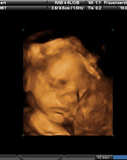

Profilbild Julian Löbbert

Julian Löbbert

* 09.05.2013 in Hamm

† 09.05.2013